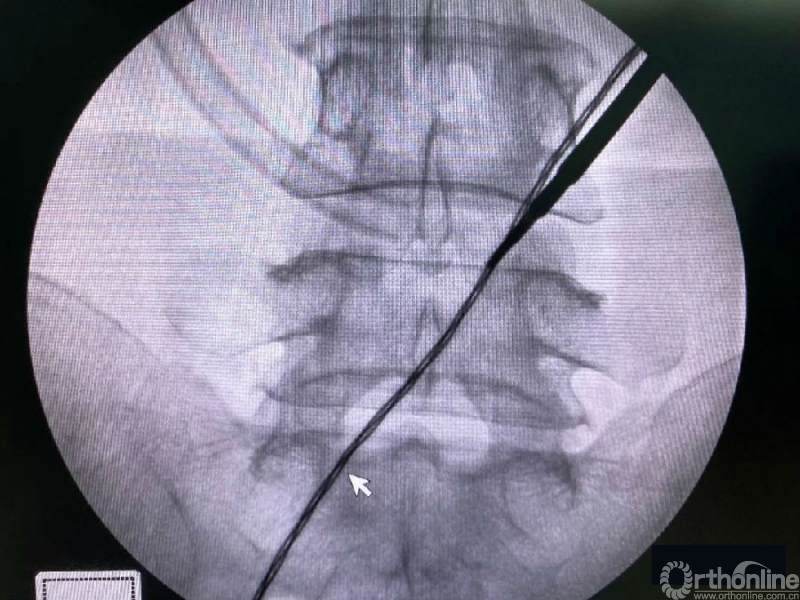

术前克氏针确定内镜口位置位于椎板稍微偏远,是一个比较理想的定位。

然后建立通道。

内镜监视下使用mark小磨钻进行第一定位,发现定位线过于偏内。

术中第一次及第二次的两个定位孔